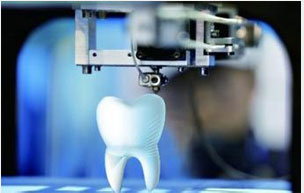

穗华3D导航模拟种植技术 精准 快速 微创

3D导航模拟种植技术

3D导航模拟种植技术

精准:采用意大利NewTom锥形束CBCT,可提供关于植入区骨(高度、厚度、宽度、骨密度)、,确保种植的位置、角度、深度与模拟效果分毫不差,建立咬合关系。

快速:种植手术整个周期由传统的6个月缩短为2个月左右,如果配合德国威兰德CAD/CAM“即刻种植,即刻负载”技术,顾客种完牙的当天就可以正常饮食。

微创:丹麦3shape3D设计系统,进行种植方案完美模拟,并打印出种植导板,医生在术前设计就能轻易地避开重要神经和血管,无需手术切口便可精准植入种植体,出血很少,把种植风险和损伤大大降低。